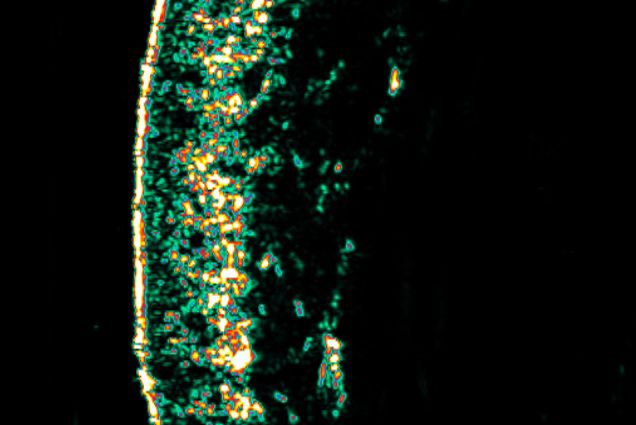

Prima del trattamento

Dopo 15 giorni di trattamento; le zone bianche rappresentano un aumento della produzione di collagene.